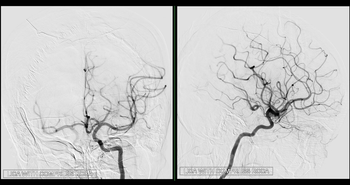

• Thrombectomie

Actualité

Plus de 180 thrombectomies réalisées en 2025 : une progression qui confirme la force du travail en r

• Actualité

Une collaboration fructueuse et durable entre le Pr Boris Lubicz et le service de Radiologie